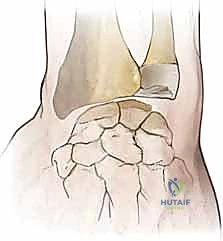

FIG 1 • A. The elements that maintain the scaphoid in its normal position, highlighting the scapholunate ligaments.